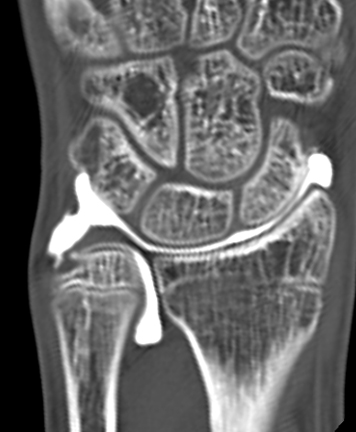

【手関節造影後CT】

単純X線の他、MRI、手関節造影/CTを行います。単純X線では、TFCC自体は映りません。しかし、骨形態の評価、とくに突き上げ症候群の評価に有用であり、必須の検査の1つです。MRIではTFCCの損傷の有無を評価します。また、ECU腱鞘炎などその他の障害/疾患の有無を確認します。しかしながら、MRIではTFCCの詳細な評価が難しい場合があり、手関節造影/CTが必要となることがあります。手関節造影/CTでは、造影剤を橈骨手根関節内および遠位橈尺関節内に注入しTFCCの円盤部や末梢部、表層部、および小窩(Fovea)部などでの断裂形態を確認します。その他、手根骨間靱帯損傷や手関節尺側部の骨形態について評価します。